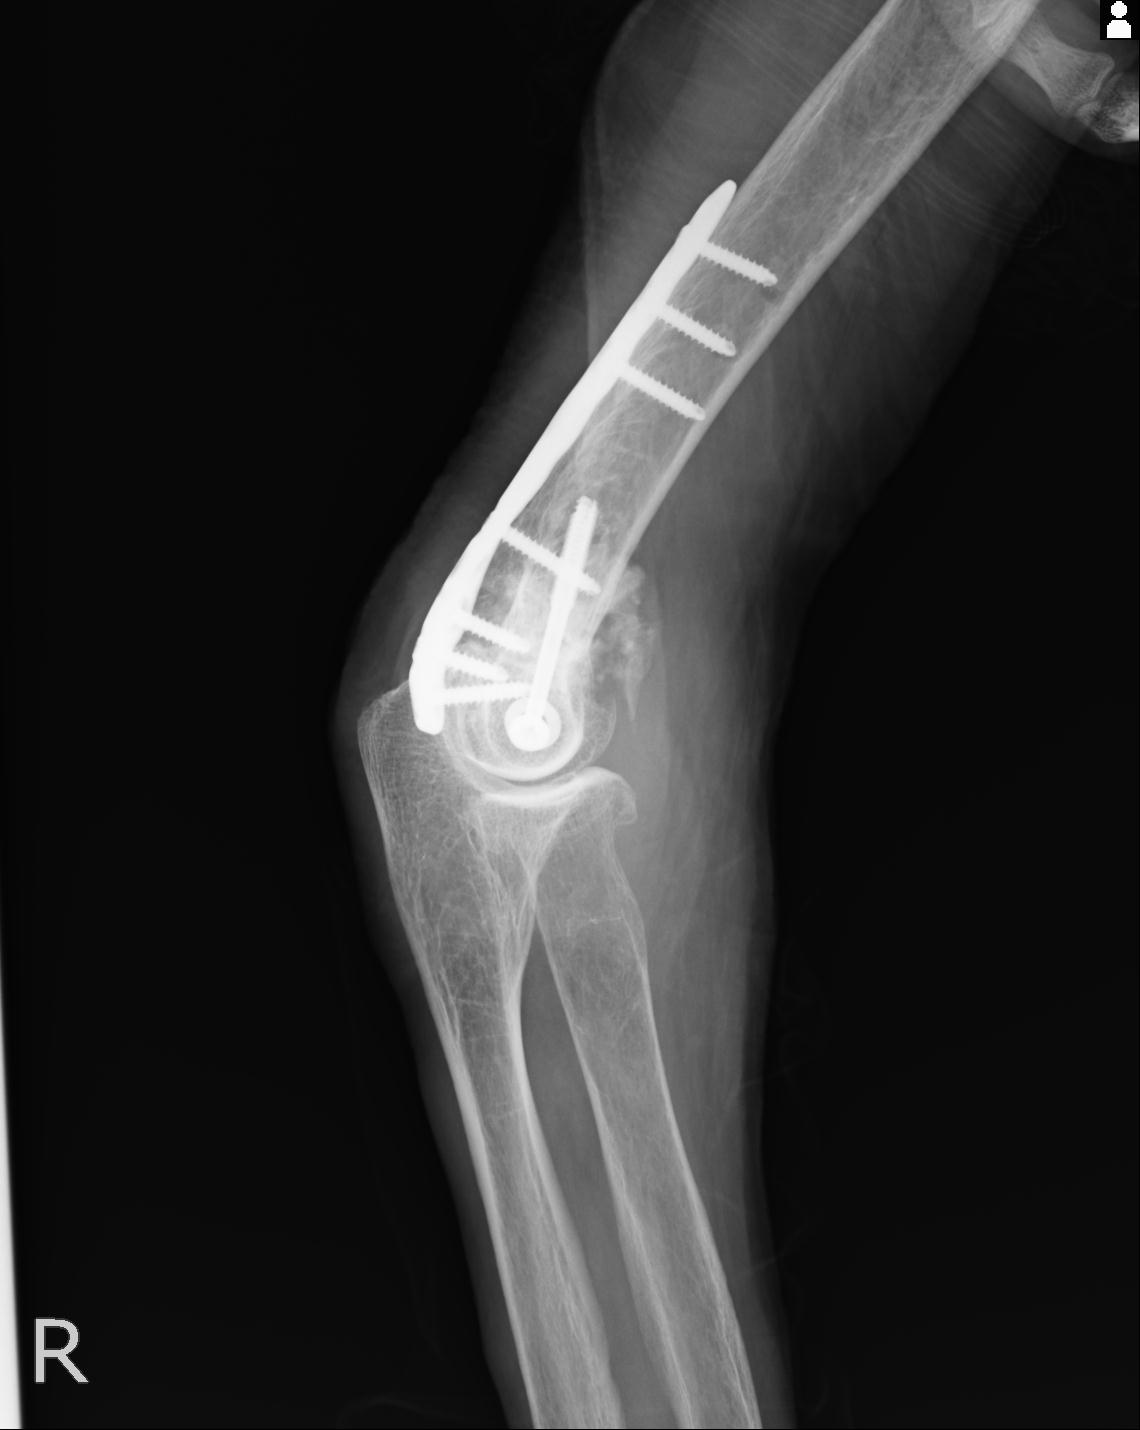

2271 1/25 右肘 4R 1/27 4R 3/24 4R 94歳女性 右通顆骨折